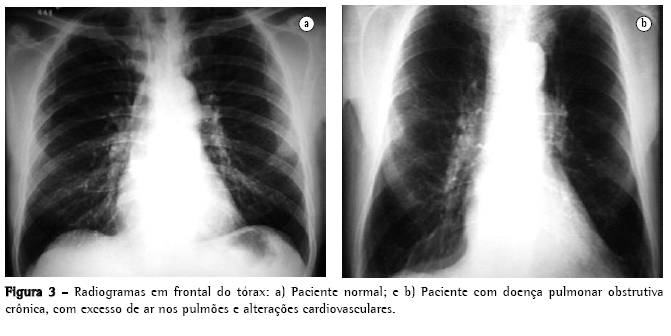

O rendimento do radiograma convencional de tórax na avaliação do enfisema é bastante limitado. Quando ainda não há aprisionamento aéreo significativo, a principal alteração é a redução da vasculatura, que somente é perceptível muito tardiamente na história natural da doença, e é um critério de extrema subjetividade. Quando há aprisionamento aéreo (Figuras 3 e 4), os critérios são mais seguros, podendo ser divididos em 3 grupos básicos de alterações,(6,8) apresentados na Quadro 1. Quando todos os critérios estão presentes, o diagnóstico é de certeza. Deve ser ressaltado que o aumento de câmaras direitas do coração, com redução da vasculatura intra-segmentar, pode também ser identificado em hipertensão arterial pulmonar, sem enfisema. Ressalta-se, também, que bolhas só estarão presentes em cerca de um terço dos casos.

Os objetivos do estudo radiológico de tórax, na avaliação do enfisema são o diagnóstico, a identificação do tipo lesional, e o julgamento da extensão da doença. Neste sentido, um estudo(6,8) traça considerações da mais alta importância:

Nos enfisemas de tipo centroacinar ou parasseptal, geralmente não há sintomatologia clínica, podendo haver aumento dos espaços aéreos, sem aprisionamento de ar nem alterações radiológicas evidentes; e

O enfisema panacinar, em geral, tem maior relevância do ponto de vista clínico, mas pode estar presente no pulmão do idoso, sem causar aprisionamento aéreo.

Alguns autores(15) relataram que o comprimento do pulmão direito e a altura do arco do hemidiafragma se correlacionavam bem com o VEF1 e a proporção VEF1/capacidade vital (CV). Neste estudo, um comprimento de pulmão direito de 30 cm ou mais identificou 70% dos pacientes com obstrução respiratória.(16) Entretanto, um autor(17) relata que todos esses estudos apresentam vícios, pois têm excesso de pacientes com obstrução respiratória crônica e, assim, as características radiológicas de obstrução aérea recebem "um valor desproporcional no reconhecimento do enfisema". Também foi demonstrado que a sensibilidade à radiografia de tórax não é boa, variando de 24(18) a 80%(19) e, também, que existe uma considerável variação intraobservadores e inter-observadores, em relação aos sinais radiológicos clássicos.(20) Os sinais radiológicos relacionados à vascularização estão sujeitos a uma variação intra ou inter-observadores ainda maior do que a dos sinais relacionados à hiperinsuflação.(19)

Um estudo comenta que o padrão enfisematoso definido pelo estudo radiológico convencional só está presente quando o enfisema é tão acentuado do ponto de vista anatomopatológico que, em geral, as reservas pulmonares já se exauriram ou estão no limite.(6,8) Uma revisão mais atualizada(22) reafirma essas proposições:

"Se os pulmões são levemente afetados por enfisema, o radiograma é freqüentemente normal";

"Enfisema pode ser diagnosticado pelo radiograma quando a doença é avançada"; e

"Somente metade dos pacientes com enfisema de extensão moderada são diagnosticáveis por radiograma de tórax."

Ambos os autores sugerem que o radiograma convencional de tórax não é um método confiável para o diagnóstico ou quantificação do enfisema.(22) Esta limitação é tão importante que alguns autores(21) demonstraram que, quando a radiologia convencional pode ser diagnóstica para doença pulmonar obstrutiva crônica, 53% dos pacientes estavam mortos em 5 anos e 70%, em 10 anos.